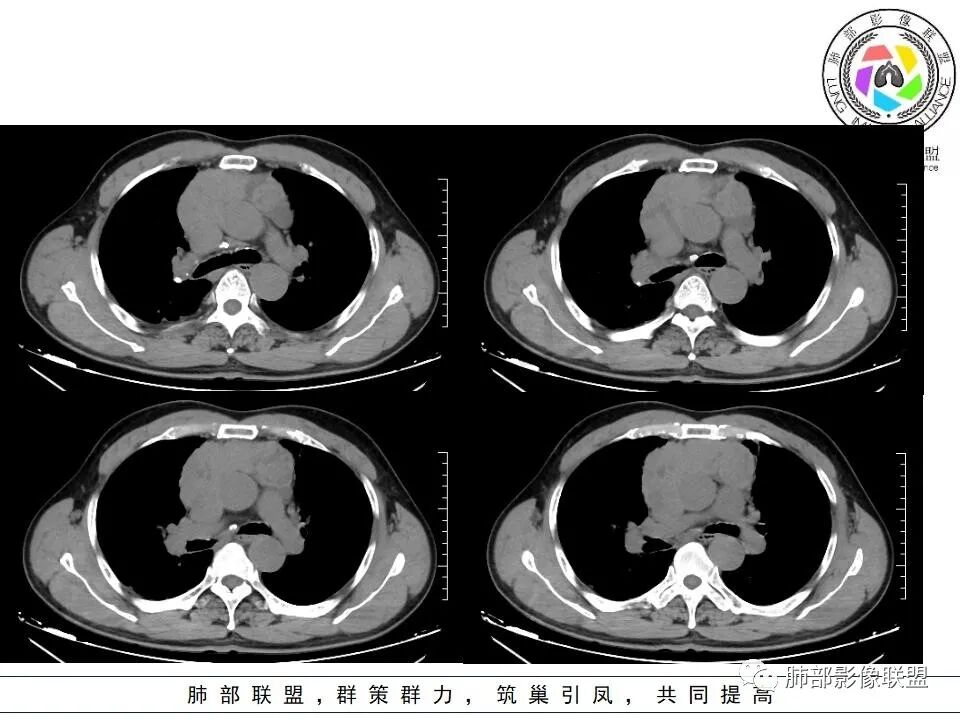

晨读:右肺上叶胸膜下实变影伴有肺大泡(结核?),前纵隔一实性肿块,骑跨主动脉生长,病变侵犯压迫腔静脉,平扫密度均匀,增强扫描均匀强化,内部可见低密度小坏死区无强化,考虑:淋巴瘤,鉴别胸腺癌(坏死偏少)

前纵隔占位,位置偏上,呈多结节融合,部分囊变,累及上腔静脉,老年男性。

晨读:男,60岁,面部肿胀一月入院,前纵隔见不规则形实性肿块影,病灶骑跨主动脉生长,部分层面与腔静脉分界欠清晰,增强扫描病灶轻度强化,病灶内见少许坏死,考虑侵袭性胸腺瘤,鉴别淋巴瘤。

晨读:男,60岁,颜面部肿胀1月入院。CT示右肺上叶条索影及实变影伴局部支气管扩张,肺大泡(陈旧性肺结核?)。前纵隔可见实性肿块,骑跨主动脉生长,平扫密度不均匀,内部可见低密度区,增强扫描渐进性不均匀强化,可见坏死区,上腔静脉受侵,考虑为恶性,侵袭性胸腺瘤或胸腺癌>淋巴瘤

晨读病例:男性患者,60岁,面部肿胀一月入院,影像表现,前纵隔实性肿块影,密度均匀,部分层面与腔静脉分界欠清晰,增强扫描病灶轻度强化,病灶内可见低密度无强化区,上腔静脉受侵犯,右侧肺门,纵膈淋巴结增大,考虑恶性病变,胸腺癌>侵袭性胸腺瘤,鉴别淋巴瘤。

晨读,老年男性,面部肿胀1月余。前纵隔肿块,边缘膨隆,见分叶,整体较均匀强化,内见小坏死,侵犯周围大血管,考虑恶性,胸腺癌可能性大。

面部肿胀(腔静脉阻塞综合征),前纵隔实性肿块,密度均匀,分叶,病灶内多个低密度区,与腔静脉分界不清晰,增强病灶轻度强化,肺门,纵膈淋巴结增大,胸腺癌?

●老年男性

●前纵隔占位明确

●上腔静脉侵犯明确

●定性恶性明确

▲上腔静脉内瘤栓

▲病灶骑跨在主动脉前缘,主动脉包绕

▲左侧边缘有强化的病灶,似乎符合坏死或囊变、或有粘液类物质。内部似有裂隙、坏死。坏死边界偏清。

▲右上叶、下叶胸膜下为主的斑片实变影,局部结构变形。支气管后移。支持慢性炎性病变,结核可能。从这个角度分析:纵隔肿瘤与肺部病灶关系不密切。

2.上纵隔增宽并见不规则块影,密度不均,轻度不均匀强化,隐约见液化密度区。

病灶边界不清,轻度分叶,后方部分紧密包绕升主动脉且侵入上腔静脉及左无名静脉末端,相应上腔静脉及左无名静脉管壁不完整。

3.右肺上叶体积缩小并见边界较为清楚的条片影及结节影,密度较高且不均,期间显示支气管扩张。

4.右肺门及纵隔见钙化淋巴结。

5.双侧胸腔未见积液。